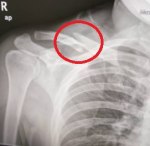

Alhamdulillah kali ini Zul berjaya bantu uruskan claim pelanggan. Claim ini dilakukan pada jun 2021. Ini adalah kes tanggalkan besi dibahu.

Pada tahun 2020 pelanggan ini mengalami kemalangan dan operation dimasukkan besi ke bahu. Kini – tanggalkan besi. Bill cecah rm11k juga. Moga beliau cepat sembuh. Amin